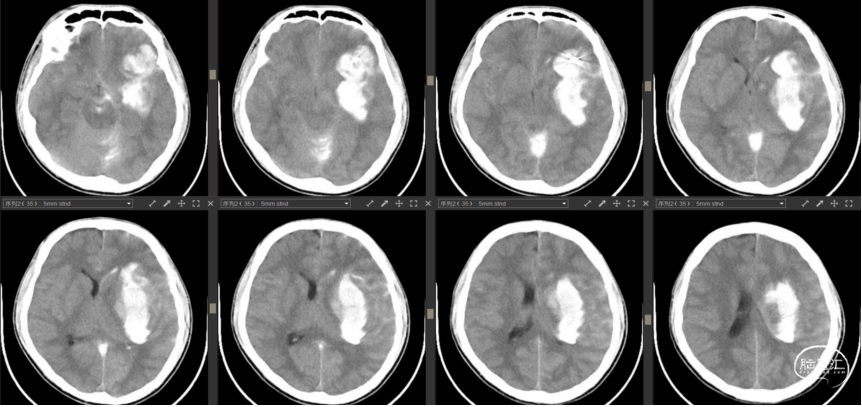

2023年7月13日

行脑动脉造影术+经导管颅内血管血栓去除术后复查CT

![]()

2023年7月14日

术后第1天CT

![]()

2023年7月21日